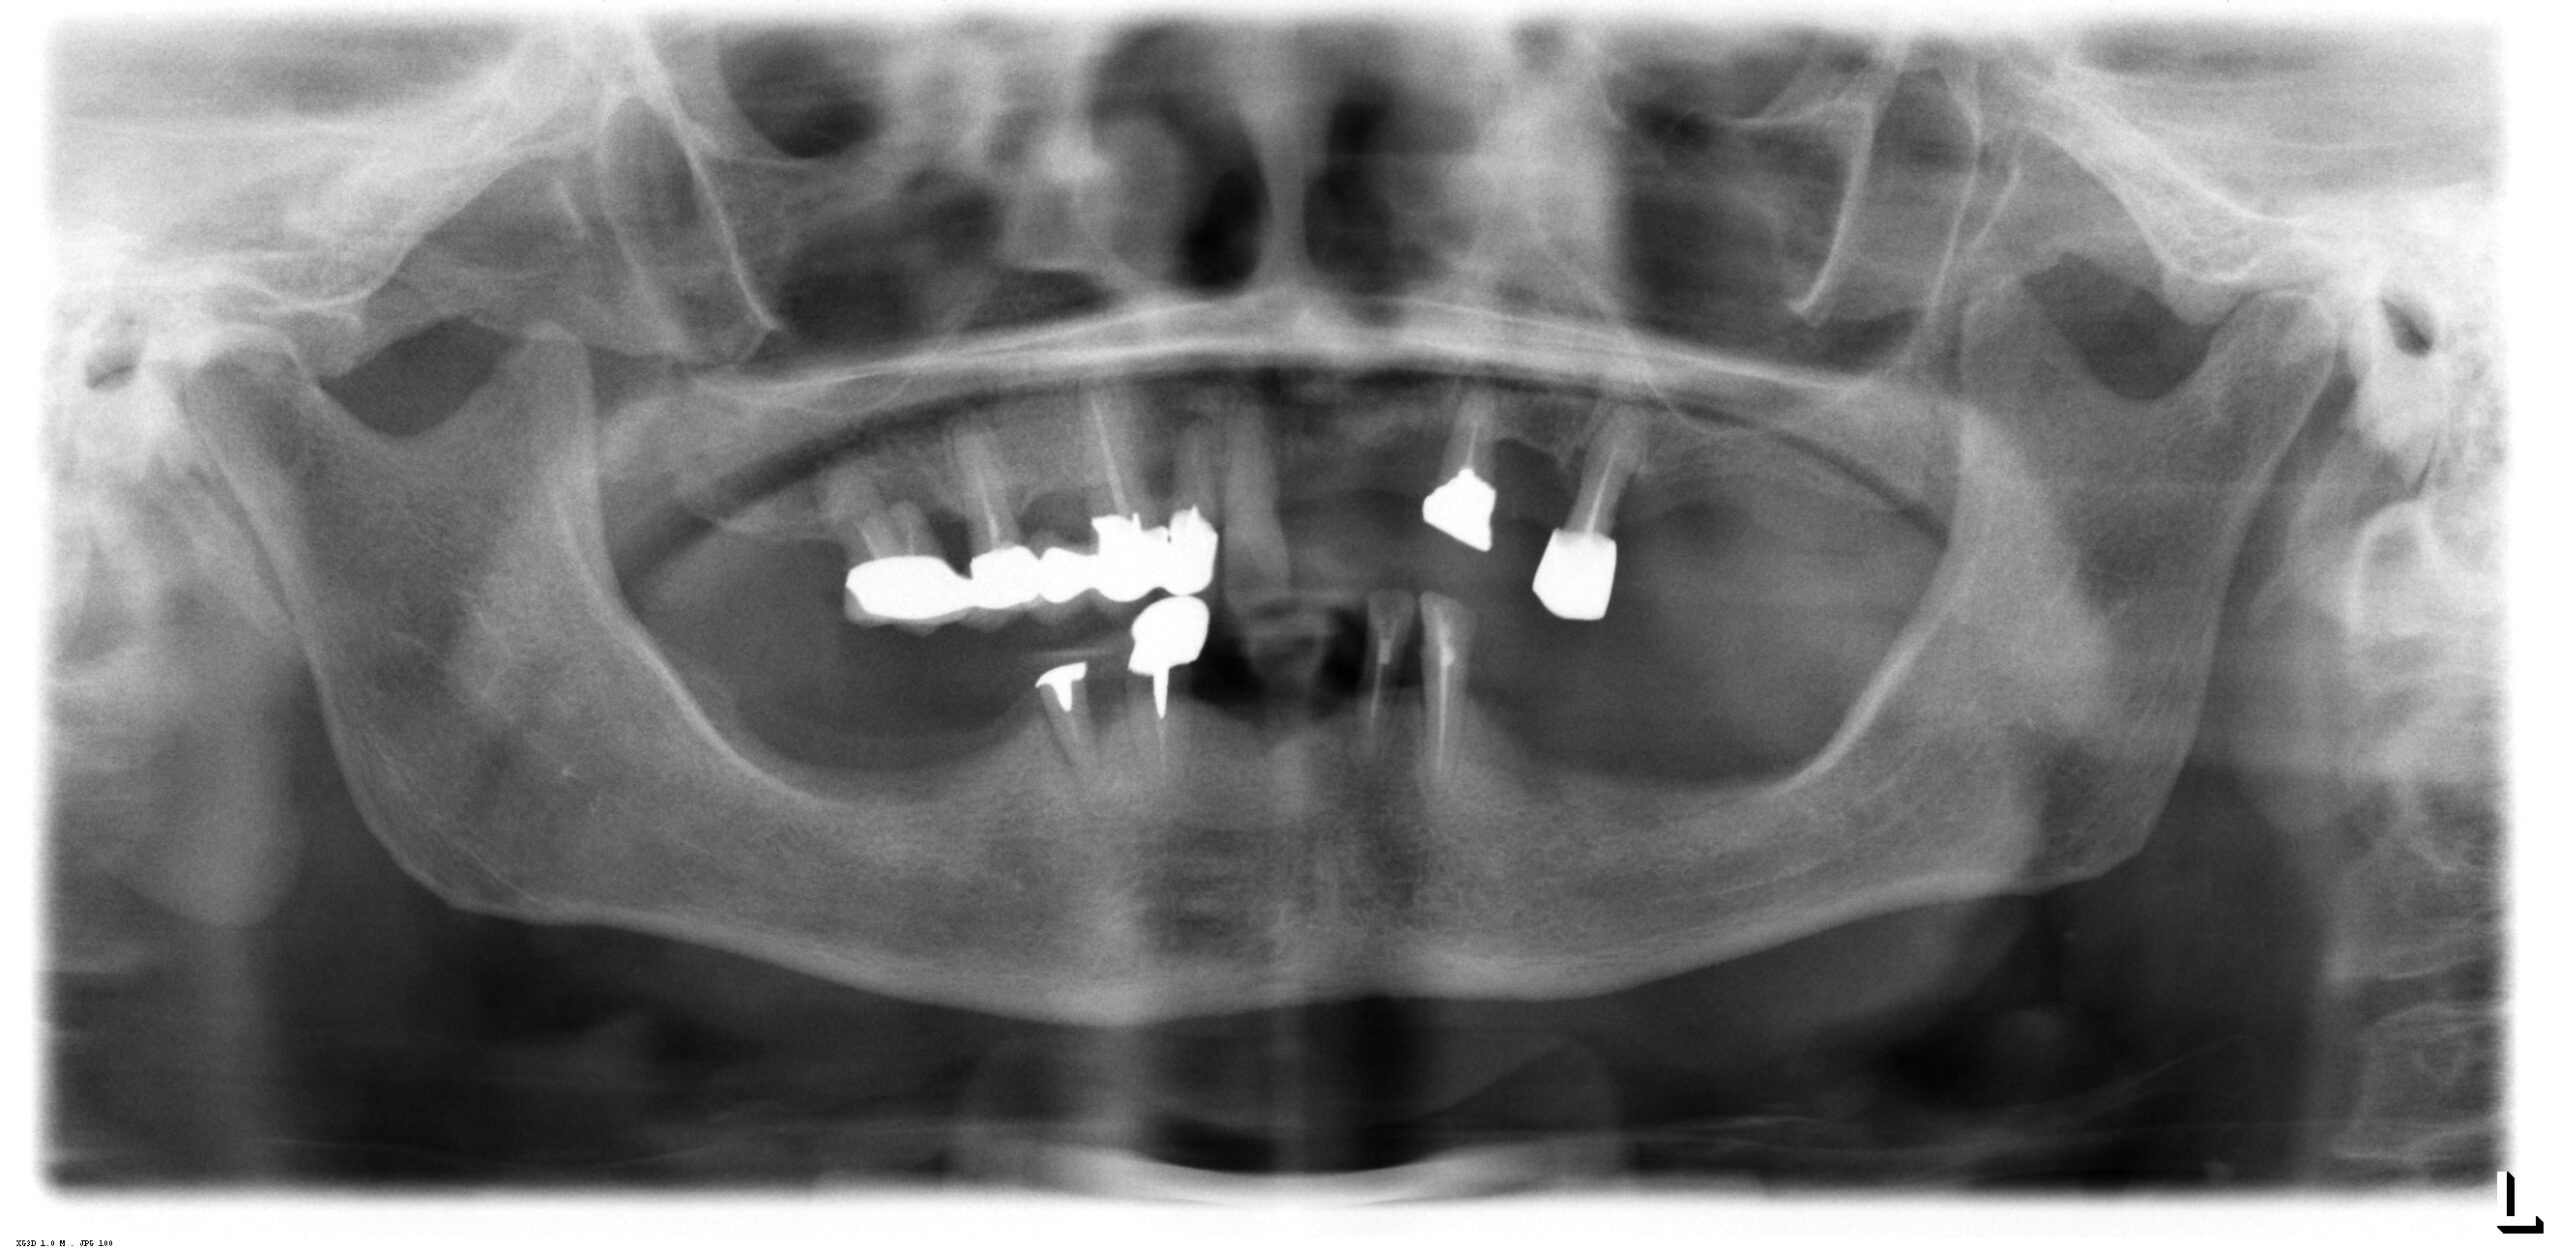

術前のパノラマレントゲン、下顎の骨は十分な高さが無いので下顎管を避けて傾斜埋入が必要でした。

歯の数が少なく、十分に咀嚼することが難しい状態です。